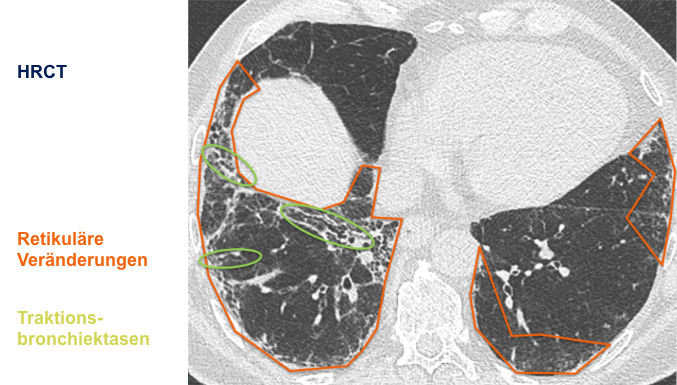

Der behandelnde Arzt hat sich für eine hochauflösende Computertomographie

(HRCT) des Thorax entschieden und folgende klinische Befundung erhoben:

Befundung des HRCT-Scans:

- Retikuläre Veränderungen

- Milchglasartige Dichteanhebungen

- Traktionsbronchiektasen

- Nicht vorhanden: Honigwabenmuster

CT: Computertomographie | HRCT: hochauflösende Computertomographie